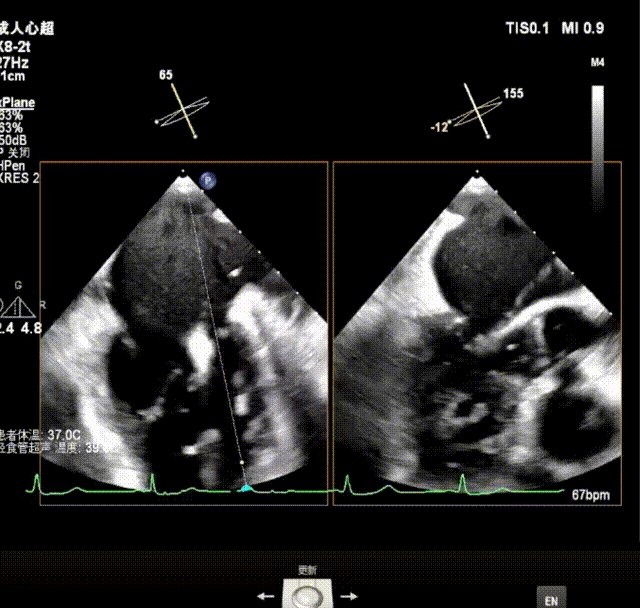

术前超声诊断

X-plane视窗可见二尖瓣2区脱垂;3D enface view示二尖瓣内P2脱垂,偏心性返流

反流束宽 15.4mm PISA半径 9mm,PISA 法估算EROA= 0.21cm²,Rvol=42ml

PW显示左肺静脉收缩期血流频谱呈逆向

3D模式测量二尖瓣瓣口面积5.57cm²;

二尖瓣口平均跨瓣压差=3 mmHg